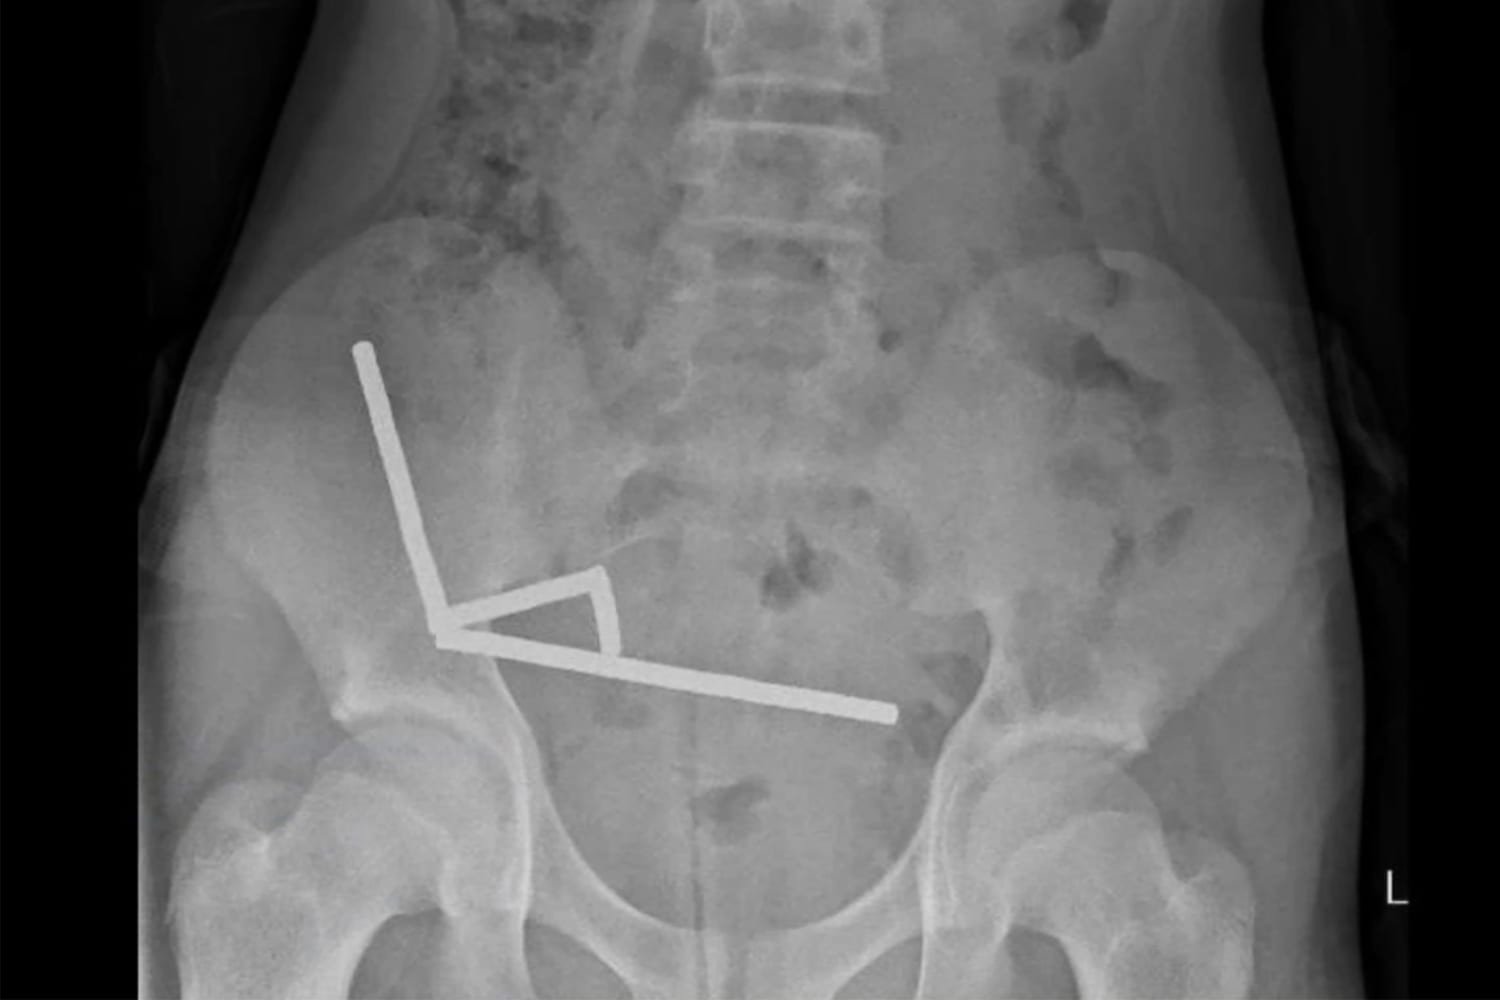

نیوزی لینڈ میں ایک 13 سالہ لڑکا تقریباً 80 سے 100 انتہائی طاقتور نیوڈیَمِیم (neodymium) مقناطیسی گولیوں کو نگل گیا۔  یہ گولیاں ایک آن لائن مارکیٹ پلیس (رپورٹ کے مطابق Temu) سے خریدی گئی تھیں۔ بچے کو چار دن تک معدے / پیٹ میں درد رہا، پھر اسپتال لایا گیا جہاں ایکس رے سے مقناطیسوں کی زنجیری شکلوں کا مشاہدہ ہوا جنہوں نے مختلف حصوں میں جمع ہو کر نقصان پہنچایا ہوا تھا۔  لڑکے کی سرجری کی گئی اور مقناطیسوں کے ساتھ ساتھ آنتوں کے اس حصے کو نکالنا پڑا جہاں ٹشوز شدید نقصان کا شکار ہوئے تھے۔  طبی ماہرین نے اس واقعے کو “بچوں کے لیے انتہائی خطرناک” اور بالخصوص آن لائن دستیابی کی وجہ سے ’لازمی روکا جانے والا اقدام‘ قرار دیا ہے۔  واضح رہے کہ جب بچے ایک سے زیادہ چھوٹے اور طاقتور مقناطیس نگلتے ہیں، تو وہ معدے یا آنتوں کے مختلف حصوں میں ایک دوسرے کے قریب آ کر “چپک” جاتے ہیں۔ یہ چپکنے والا عمل ٹشوز کے درمیان دباؤ پیدا کرتا ہے، خون کا بہاؤ متاثر ہو سکتا ہے، ٹشوز مردہ پڑ سکتے ہیں اور ردّعمل کے ساتھ بندش یا سوراخ بھی ہو سکتا ہے۔